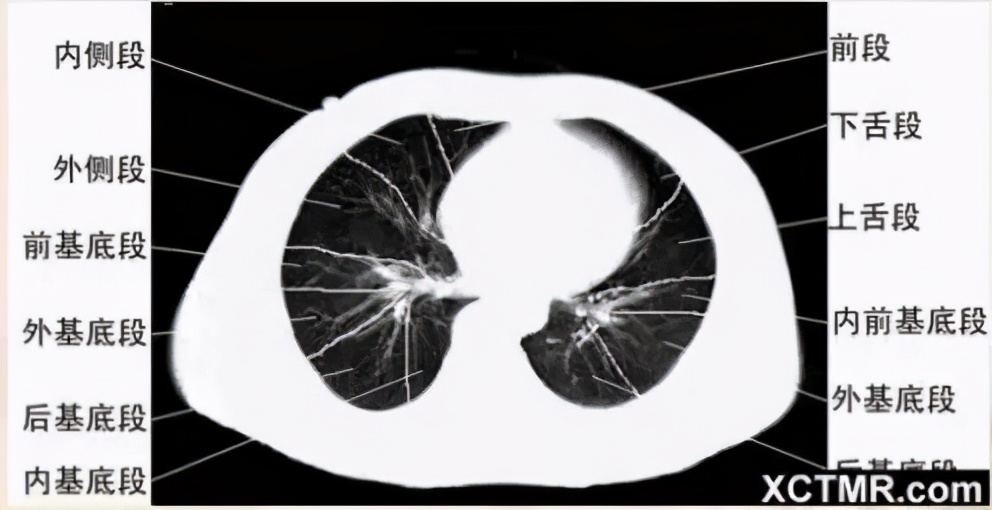

肺段划分